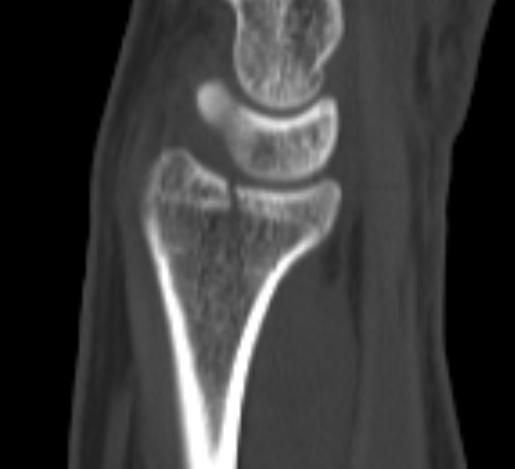

손목 요골 원위부 골절 문의드립니다.

약 3주전 넘어지는 사고로 손목 골절 진단 받고 1주 반깁스 후 통깁스 치료 중입니다.

아래는 사고 당시 X-ray 와 CT, MRI 사진입니다.

• 2번 째 사진

요골 원위부 골절은 골절의 모양, 전위 정도, 관절면 침범 여부에 따라 치료방침이 달라집니다.

엑스레이 및 CT에서 저누이가 심하지않고 관절면에 영향이 없다면 보존적 깁스 치료로도 충분히 잘 붙는 경우가 많습니다. 다만 고령, 골다공증, 분쇄골절, 관절면 불일치 시엔 추후 통증 기능장애 가능성이 있어 수술이 고려됩니다.

• 올리신 사진 세 장을 놓고 진료를 받으신 병원들만큼 자세하게 파악하고 정확한 판단을 내려드릴 수는 없습니다. 사진들을 보았을 때에는 변형이 심하게 생기거나 해 보이지 않기 때문에 손목 가동범위에 문제가 있거나 신경 손상 등을 의심할만한 소견이 없다면 수술적 치료 없이도 회복이 가능할 수도 있겠다 추측해볼 수도 있겠습니다. 그렇지만 앞서 언급하였듯 정확히 어떻다 이야기 하기는 어렵습니다.